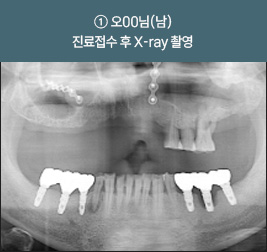

I      올온포 풀아치 임플란트 사례     I

치료 기간 : 2021.03.12 ~ 2021.08.25